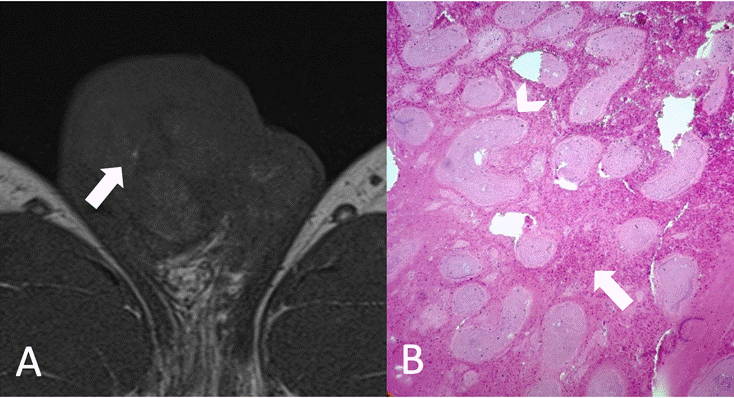

A) Imagen axial secuencia T1. Áreas puntiformes hiperintensas vinculables a microhemorragias por estasis sanguínea (Flecha). B) Parénquima testicular constituido por túbulos seminíferos necróticos (Cabeza de flecha) rodeados por un estroma con microhemorragias e infiltrado inflamatorio linfocitario (Flecha). Origen: Servicio de Diagnóstico por Imágenes. Hospital Italiano de Buenos Aires. Buenos Aires, Argentina. 2021.

Figura 4a Comparación RM-histopatología.